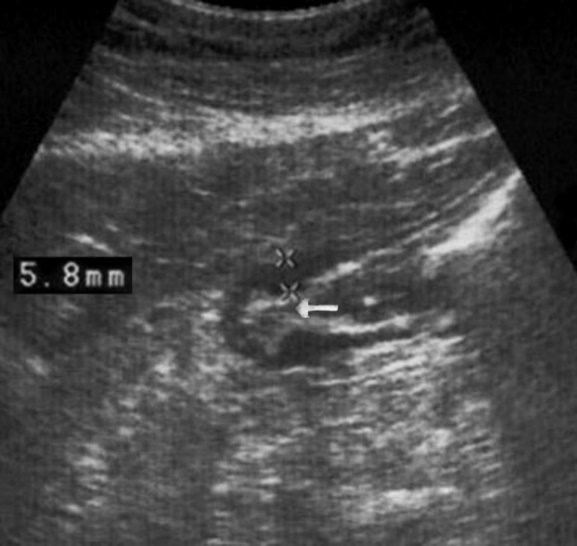

The polypoid type of gastric cancer was observed in 3 (4,9±2,8%) cases, the ulcerative type – in 18 (29,5±5,8%), the infiltrative ulcerative type – in 27 (44,3±6,4%) and the diffuse infiltrative type – in 13 (21,3%±5,2%) cases respectively (Table 2). On the echogram, the tumor was

Visualized as a polypoid formation on a wide base above the gastric mucosa of a non-uniform structure, an irregular surface (Figure 5, Figure 6, Figure 7).

Figure 5.The polypoid type of gastric carcinomas for T3 stage. On the posterior wall of the antrum, a polypoid formation with a fuzzy contour is visualized, the image of the mucous and serous membranes (arrows) is discontinuous.

Figure 6.The gastric carcinoma for T3 stage. The tumor is visualized as a polypoid formation on a wide base above the gastric mucosa of a non-uniform structure, an irregular surface (arrows).